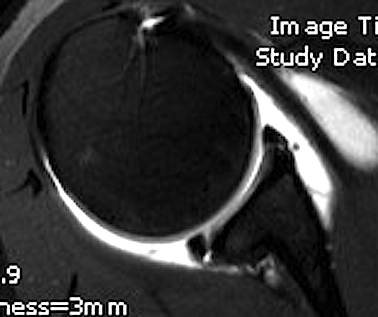

MRI

Posterior labral tears / bankart lesion

Posterior labral tear

Posterior labral tear

Kim lesion

- Kim lesion

- incomplete and concealed avulsion of the posteroinferior labrum

- superficial portion attached, deep portion detached

- labrum flat with loss of normal height resulting in retroversion of the chondrolabral glenoid